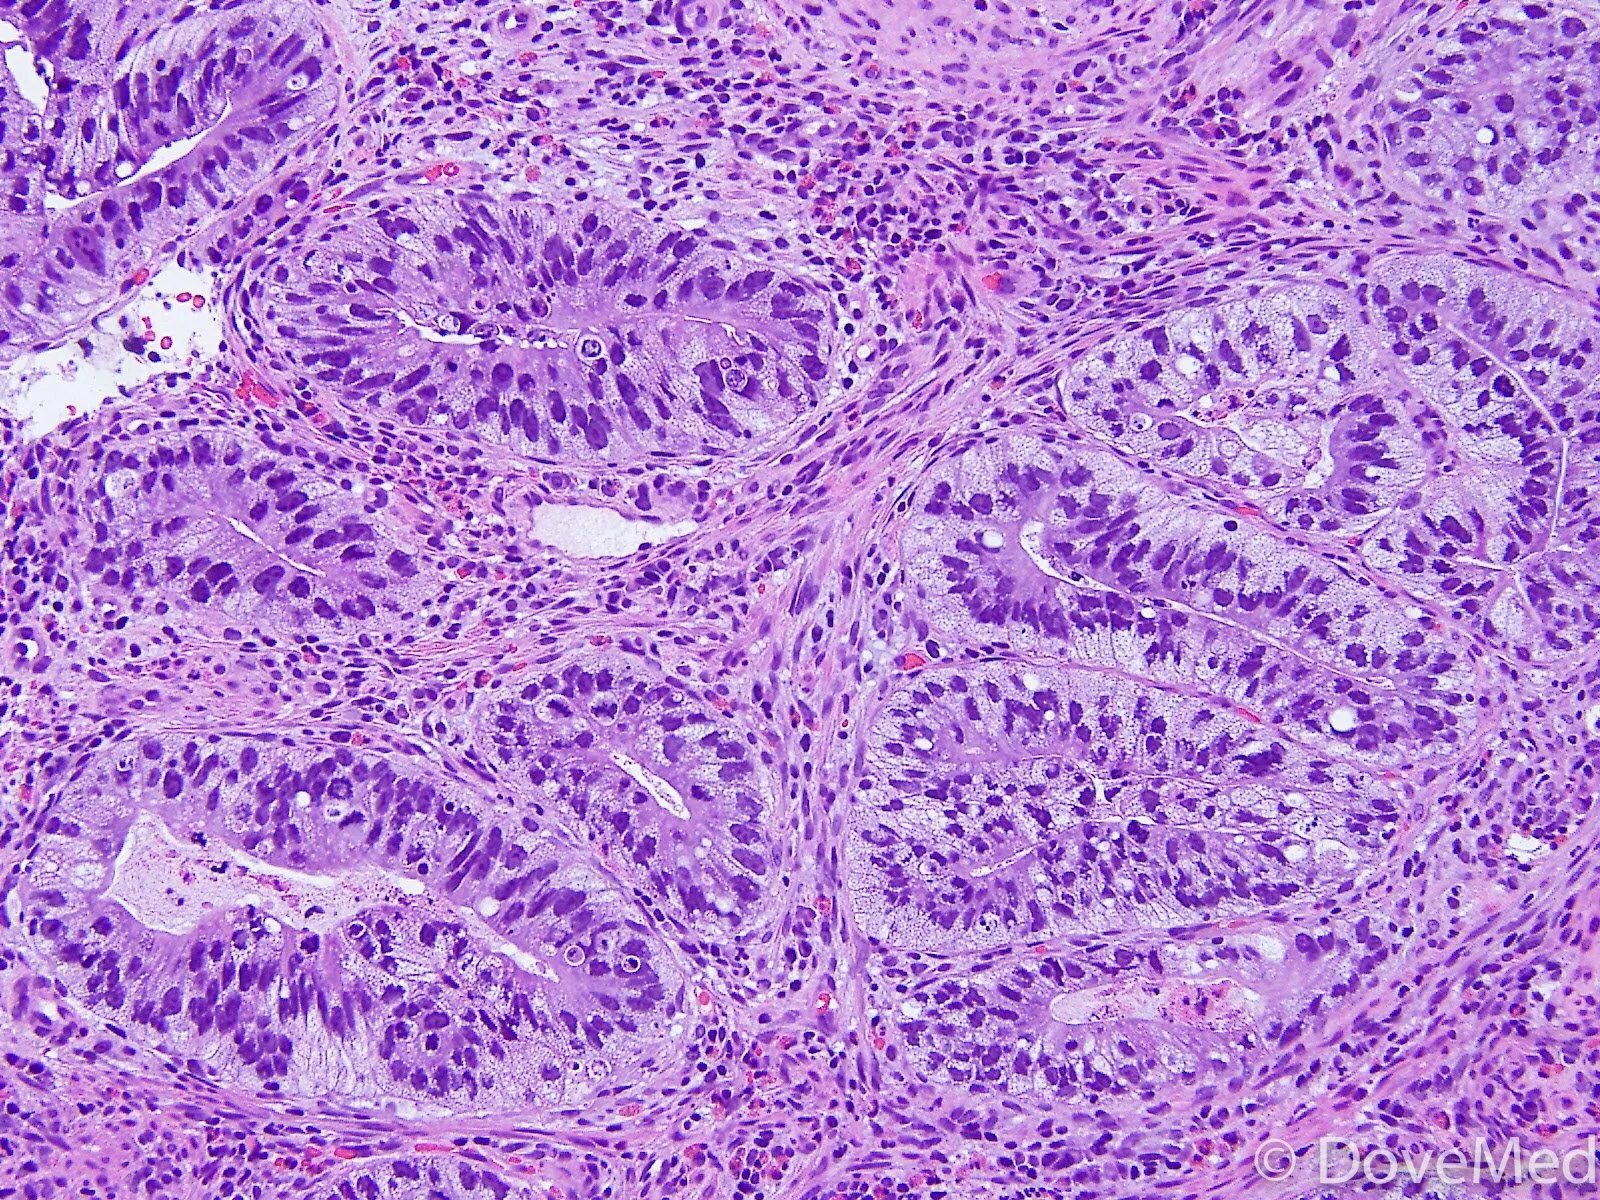

Что показала гистология замершей